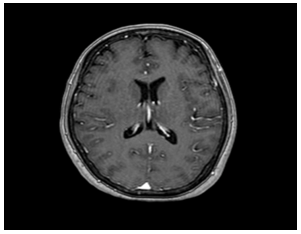

- Cộng hưởng từ sọ não:

Hình 5: Hình ảnh cộng hưởng từ sọ não: chưa phát hiện tổn thương thứ phát

- Cộng hưởng từ sọ não: Không phát hiện tổn thương bất thường.